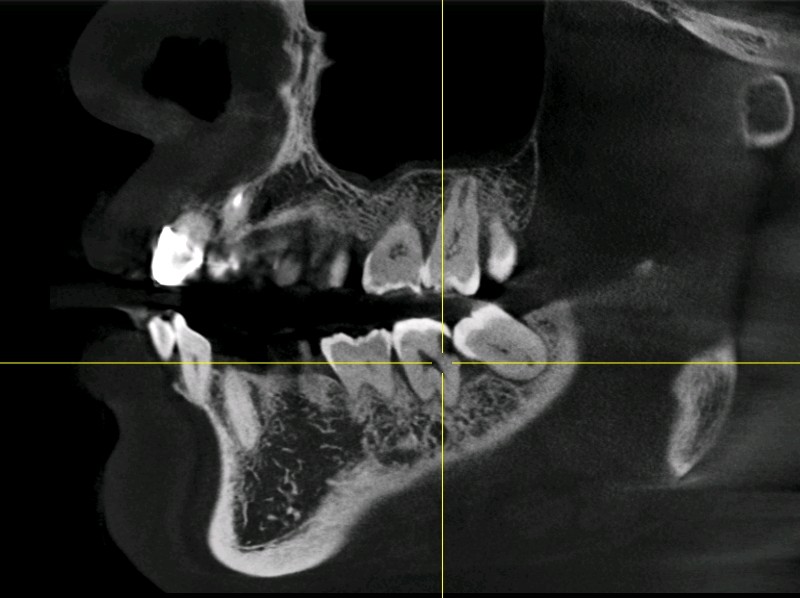

那么一般什么样的智齿需要拔除呢?1、阻生齿或和相邻磨牙接触不正常的智齿。2、咬腮智齿3、对颌没有牙,没有咬合功能的智齿。4、智齿本身存在牙体疾病。

对于以上这些智齿如果不拔除会有哪些危害呢?1、会顶坏邻近牙齿。常常塞牙导致邻牙龋坏或者牙槽骨吸收。2、容易引起智齿冠周炎。智齿萌出不全异位或者阻生。牙龈与牙体之间容易形成一个狭窄较深的盲袋。易积攒食物残渣滋生细菌。时间长了就会造成智齿冠周炎起疼痛,肿胀,张口受限,严重了会导致间隙感染。3、影响咬合。智齿萌出位置异常,导致咬合关系错乱,影响颞下颌关节的正常活动。4、位置靠后不易清洁,食物残渣堆积容易发生龋坏,长期以往会发展成牙髓炎,发生疼痛的现象。